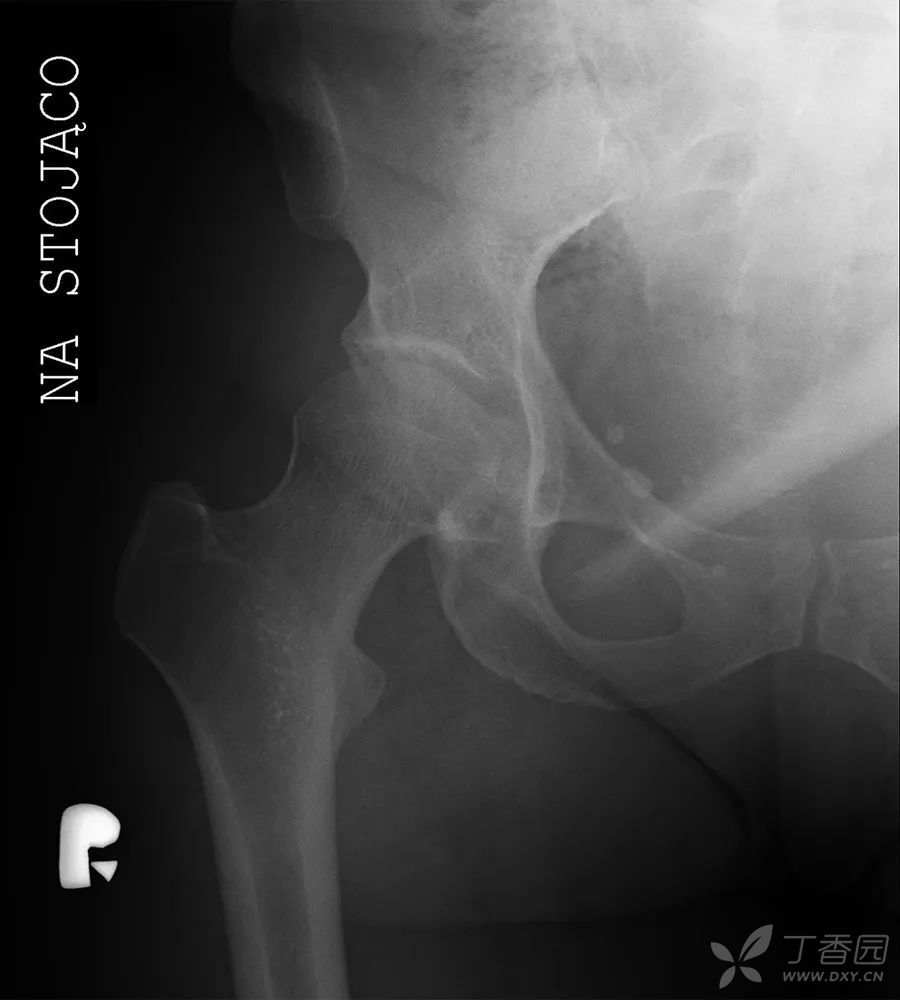

髋关节X线检查

腹腔CT